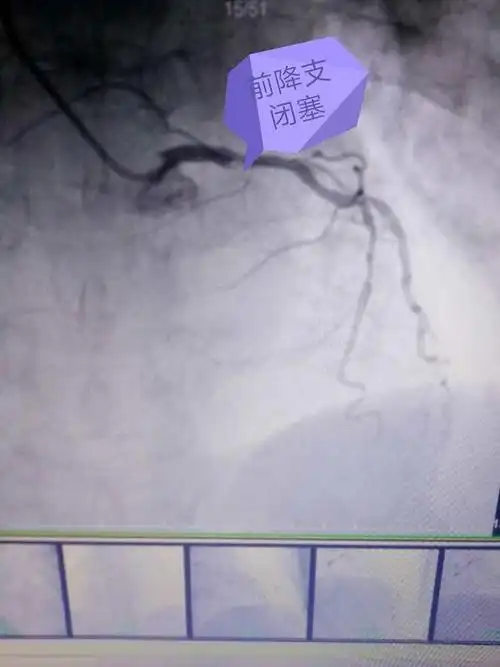

造影显示前降支闭塞